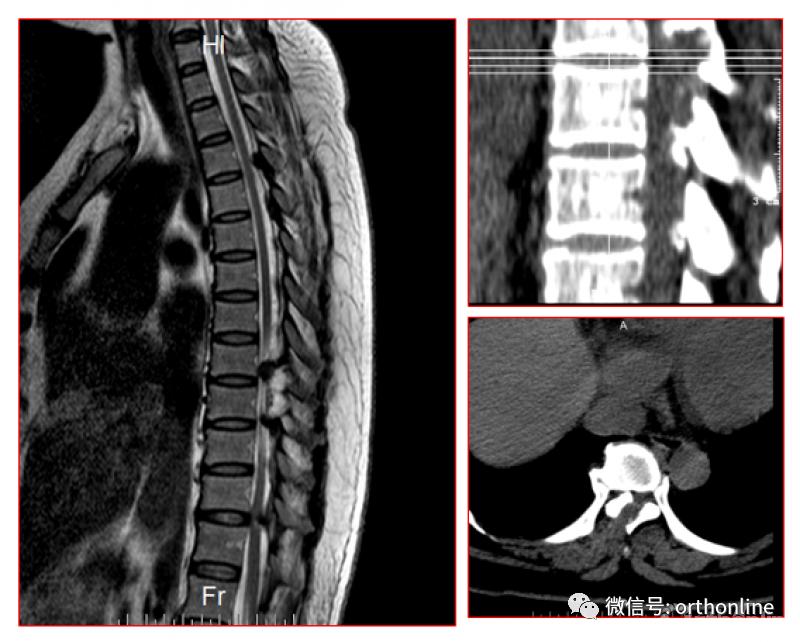

二、后纵韧带骨化形态学分型

1.按照矢状位CT分为线型、鸟嘴型、连续波形、连续圆柱形和混合型。

OPLL的CT矢状位分型为A.线性(Linear type);B.鸟嘴型(Beak type);C.连续波形(Continuous waveform type);D.连续圆柱形(Continuous cylindrical type)。混合型(Mixed type)为同时具有A-D两种及以上类型

脊柱内镜手术通常作为首选手术方法,能有效地减压并进行相应的处理。适用于胸椎管狭窄症,如胸椎黄韧带肥厚症、胸椎间盘突出症、胸椎后纵韧带骨化症等,尤其适合单节段狭窄者。